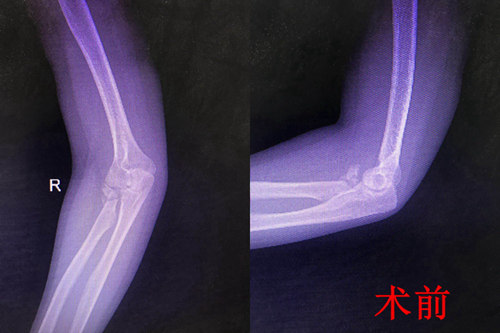

『市内首例』骨一科成功完成一例右桡骨小头粉碎骨折人工桡骨小头置换术

近日,我院骨一科成功完成一例右桡骨小头粉碎骨折人工桡骨小头置换术,该项技术的成功开展填补了我院乃至全市人工桡骨小头置换术的空白。

患者,青年女性,摔伤致右肘部疼痛伴活动受限1月余入院。入院后行拍片、CT检查示:右桡骨小头粉碎骨折。

考虑到患者系粉碎骨折,科室立即组织会诊讨论,最终决定由副院长杜敏指导,科室副主任张延平主刀,主治医师王陇协助行人工桡骨小头置换术,手术过程顺利,无并发症发生,术后患者病情平稳。目前患者前臂已行旋转功能锻炼,恢复良好。